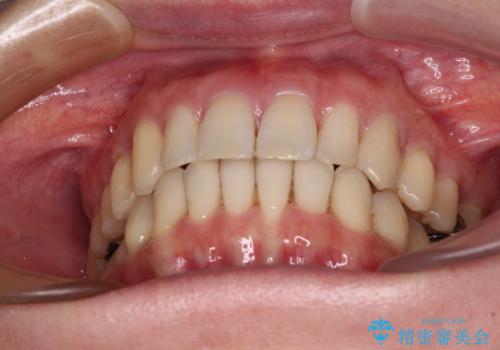

八重歯のインビザライン矯正治療

- 下顎の八重歯と、上下のクロスバイトを気にして来院された患者様です。

インビザラインを用い、下顎全体の後方移動、IPR(歯と歯の間を削る)と歯列全体を拡大させることで、歯並びを整えていくこととしました。

奥に位置していた上の前歯が下の前歯を乗り越える際、奥歯でものを咬むことができず、辛い時期が続きました。